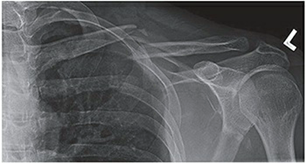

Radiographic Evaluation and Templating

Standard radiographic evaluation includes an anteroposterior (AP) view of the clavicle and a 15 to 20 degree cephalic tilt view. The cephalic tilt view projects the clavicle free from the underlying ribs and provides a more accurate assessment of superior-inferior displacement and shortening. In cases of severe comminution, marked displacement, or suspected intra-articular extension into the sternoclavicular or acromioclavicular joints, a computed tomography (CT) scan with 3D reconstructions is highly recommended. CT imaging provides precise characterization of butterfly fragments and aids in determining the appropriate length and contour of the fixation construct.

Image

Pre-operative templating should be performed using digital software to estimate plate length, screw sizes, and the necessity for lag screws. The surgeon must evaluate the bone quality and the location of the fracture relative to the medial and lateral ends of the clavicle to ensure adequate cortical purchase can be obtained on both sides of the fracture. Generally, a minimum of three bicortical screws (six cortices) on each side of the fracture is required for stable plate osteosynthesis.